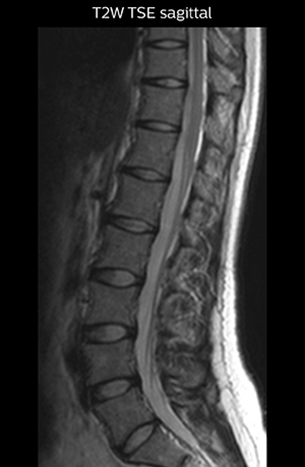

The key concept in MR neurography, Dr. Yabuki stresses, is the ability to directly visualize spinal nerves, versus inferring the presence of pathology indirectly. “Before NerveVIEW, we estimated compression of the nerve by looking for the presence or absence of fat signal on other MR images,” he says.

“For example, in sagittal images, when the presence of fat is observed in the intervertebral foramen, it suggests that there is a margin around the nerve. Similarly, the absence of fat indicates that the nerve is being compressed. So, we used to deduce nerve compression indirectly. With NerveVIEW, however, we can observe the condition of the nerves directly, regardless of the presence or absence of fat. We always prefer such direct observation of anatomy over having to make an inference about it.”